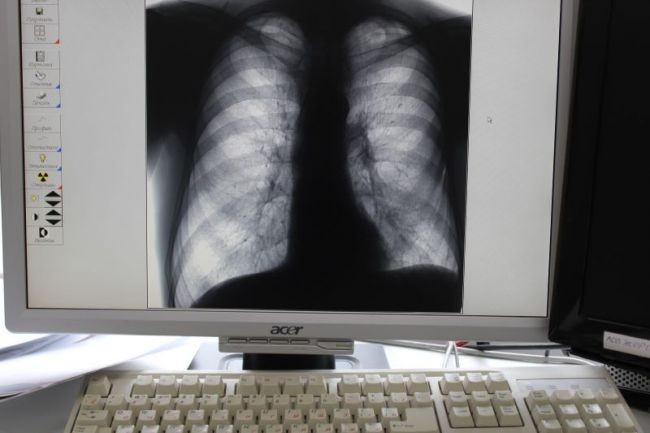

В наше время все более распространено невнимательное отношение к своему здоровью, что может иметь серьезные последствия. Один из распространенных примеров такого невнимания - это неправильное лечение или отсутствие лечения простуды и бронхита, что может привести к развитию серьезных осложнений, таких как воспаление легких.

Простуда и бронхит часто сопровождаются кашлем, насморком, болью в горле и общими недомоганиями. В большинстве случаев эти заболевания являются вирусными и сами по себе не требуют антибиотиков. Однако, при неправильном лечении или отсутствии лечения, воспаление может перейти в легкие, вызывая пневмонию или другие серьезные заболевания.

Осложнения в виде воспаления легких могут привести к сильному кашлю, большой слабости, одышке, жару и другим симптомам, требующим серьезного лечения. В худших случаях, воспаление легких может вызвать острую дыхательную недостаточность и привести к летальному исходу.